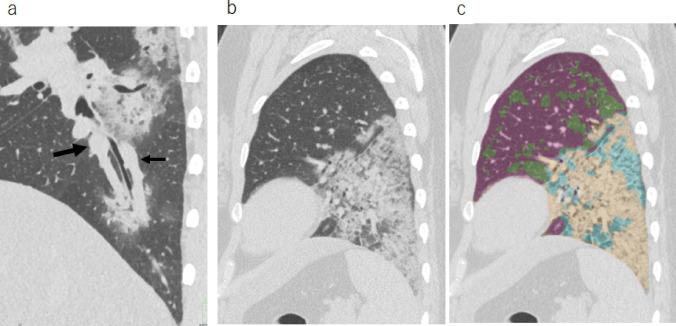

Ultra-high-resolution (UHR) CT images of 87 patients (50 males, 37 females; median age, 63 years) with COVID-19 confirmed using real-time polymerase chain reaction were analyzed. The maximum subsegmental vascular diameter was measured on CT. Total CT lung volume (CTLV total) and lesion extent (ratio of lesion volume to CTLV total) of ground-glass opacities, reticulation, and consolidation were measured using software. Maximum pulmonary vascular diameter and lesion extent were analyzed using Spearman's correlation analysis. Logistic regression analysis was performed on CT results to predict disease severity. We also assessed changes in these measures on follow-up scans in 16 patients.

All 23 patients with severe and critical illness had vascular enlargement (> 4 mm). Pulmonary vascular enlargement (odds ratio 3.05, p = 0.018) and CT lesion extent (odds ratio 1.07, p = 0.002) were independent predictors of disease severity after adjustment for age and comorbidities. On follow-up CT, vascular diameter and CT lesion volume decreased (p = 0.001, p = 0.002; respectively), but CTLV total did not change significantly.